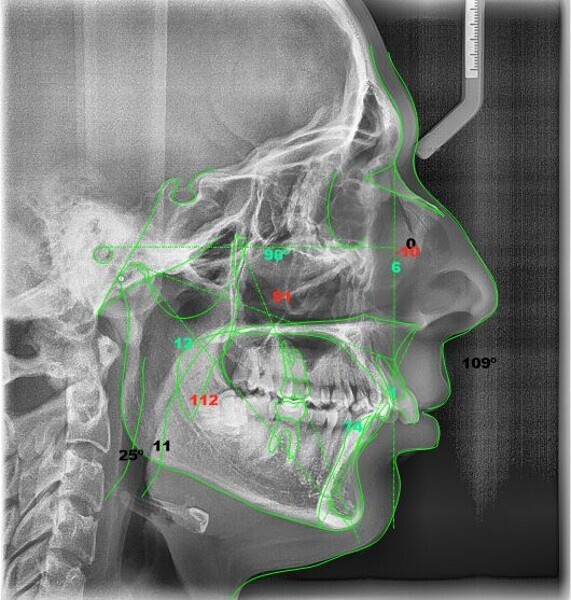

In the radiographic analysis, the dental panoramic tomogram revealed that the two mandibular third molars were unerupted and horizontalised in the mandible. Nothing else relevant was observed in the radiograph (Fig. 3). A cephalometric radiograph was used to perform the cephalometric analysis according to Steiner,6 Ricketts7, 8 and McNamara9 (NemoCeph Studio, Nemotec Fig. 4).

In the Steiner analysis, the SNB angle of 74° suggested mandibular retrusion. Likewise, the ANB angle of 7° indicated Class II, which was also confirmed by Wits analysis (8.3 mm). The results indicated a protrusion of the maxillary incisors and a decreased inter-incisal angle of 118°, which suggested protrusion of the maxillary and mandibular incisors (Fig. 5).

In the Ricketts analysis, a dolichofacial pattern, that is, a facial axis of 84°, was diagnosed. The analysis also confirmed the protrusion of the incisors (Fig. 6).

The McNamara analysis revealed that the size of the mandible that would correspond to the dimensions of the maxilla (91.0 mm) would be between 114.0 mm and 117.0 mm and not the current size of 111.9 mm,9 indicating that the mandible was smaller than it should have been. However, the maxillomandibular difference was 20.9 mm, indicating a Class II skeletal pattern (Fig. 7). From the aforementioned information, we determined a Class II skeletal pattern and dental relationship with retrusion of the lower jaw and an increased overjet and overbite.